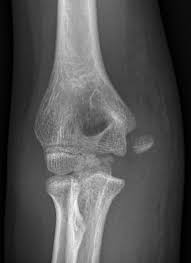

Medial epicondyle fractures represent almost all epicondyle fractures and occur when there is avulsion of the medial epicondyle. They are typically seen in children, and can be challenging to identify. Ligaments connect bones to other bones. Random house webster's unabridged english dictionary. It is amazing when the importance of the small parts, mostly unrecognized things, of the living world is considered. From wikipedia, the free encyclopedia. It is larger and more prominent than the lateral epicondyle and is directed slightly more. The epicondyle is something similar to the condyle but is present on the outer surface on top of the condyle, it does not have any direct connection there are many epicondyles present in a human body, and they have different characteristics. Example sentences from the web for epicondyle. The medial epicondyle of the femur is an epicondyle, a bony protrusion, located on the medial side of the femur at its distal end. 16% calcification along lateral epicondyle 19. From wikipedia, the free encyclopedia. There are various epicondyles in the human skeleton, each named by its anatomic site.

If the symptoms are related to a neck problem, an mri scan may be ordered. A rounded projection at the end of a bone, located on or above a condyle and usually serving as a place of attachment for ligaments and tendons. They are typically seen in children, and can be challenging to identify. Epicondyle refers to a protuberance on the condyle of a long bone. 16% calcification along lateral epicondyle 19.

Epicondyle synonyms, epicondyle pronunciation, epicondyle translation, english dictionary definition of epicondyle. It is larger and more prominent than the lateral epicondyle and is directed slightly more. Condyle meaning knuckle or rounded articular area(wiki) often refered to as the medial or lateral epicondyle of the knee. Choose from 175 different sets of flashcards about epicondyle on quizlet. An epicondyle is a rounded eminence on a bone that lies upon a condyle. Cranial to the medial epicondyle, the median nerve passes between the origins of the pronator teres and biceps brachii muscles. Failure to diagnose these injuries can lead. Epicondyle definition, a rounded protuberance at the end of a bone, serving as a place of attachment for ligaments, tendons, and muscles.